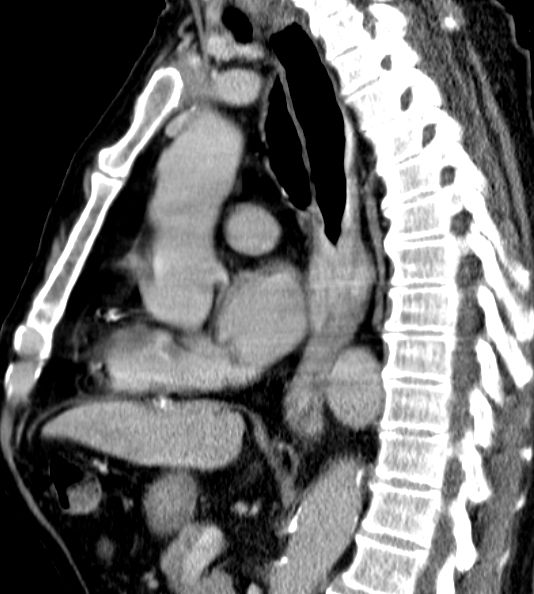

Lokale Ausbreitung im Mediastinum, Lymphnoten-Metastasen in der CC-Achse, Lungen- und Lebermetastasen.

Endoskopie mit Biopsie, Rö.-Breischluck, CT oder MRT

Technik von der Lokalisation abhängig. Rekonstruktion durch Magenhochzug oder Coloninterponat.